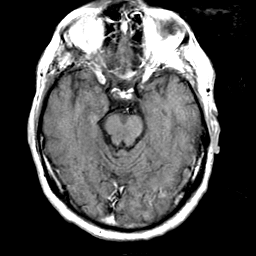

Meningioma, MR Study #1 -- Slice #7

[Home][Help][Clinical] Slice 7